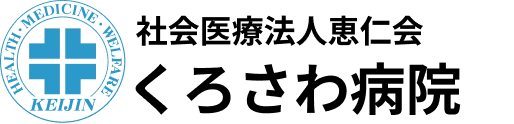

脚の付け根の骨折=大腿骨近位部骨折には大きく分けて3つあります(図1)。一つは大腿骨頭のすぐ根元で折れる大腿骨頚部骨折、ずれがあるかどうかによって治療法が異なります。次に大転子と小転子と呼ばれる二つの出っ張りの間で骨折する大腿骨転子部骨折で骨折の程度はさまざまです。最後に大腿骨転子下骨折といって先ほど説明した転子部骨折より下で起こる骨折です。